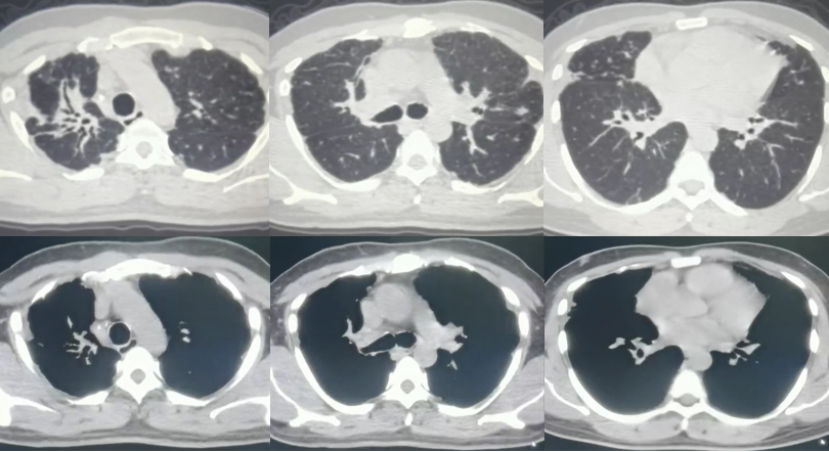

诊断“间质性肺炎,慢阻肺急性加重期,支气管扩张,Ⅱ型呼吸衰竭”。抗感染20 d,激素治疗20 d(图9),鼻导管氧疗及NPPV。咳嗽、喘息明显减轻。胸部CT:对比10月26日,双肺斑片影、磨玻璃影明显吸收(图10)。11月17日评估病情好转出院,出院后继续口服甲泼尼龙12 mg qd(11月17-30日,13 d后自行停药)。

治疗调整(2021年12月4-19日):12月4日(停激素4 d)患者自觉喘息较前加重,再次就诊于当地市医院门诊,胸部增强CT:双肺斑片影较11月9日略吸收,双侧胸膜增厚如前(图11)。12月4日加用环磷酰胺50 mg qd至12月17日患者自行停用,并再次应用甲强龙24 mg qd,于12月18日减量至12 mg qd(图12)。

第5次住院(2021年12月20-24日):12月20日(甲强龙12 mg维持治疗中)受凉后再次出现咳喘加重,伴发热,体温38.0℃,伴肌肉、关节酸痛,流清涕,于当地市医院住院。血常规:WBC 11.46×109/L(↑),NEU 8.47×109/L,LYM 1.07×109/L,血红蛋白168 g/L,血小板327×109/L。血气分析(FiO2 0.41):pH 7.40,PaO2 115.5 mmHg,PaCO2 60.5 mmHg(↑),PFR 280 mmHg(↓),HCO3- 36.2 mmol/L。12月20日胸部CT:双肺新发散在淡薄渗出斑片影,部分结节影,较12月4日加重(图13)。予比阿培南、依替米星、莫西沙星抗感染治疗(图14),患者体温恢复正常,咳喘无改善,于12月24日转至我院。